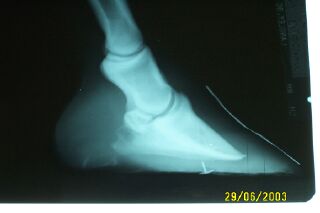

Posted on Monday, Jun 30, 2003 - 6:55 pm: Dr. O - I just had my geldings front feet exrayed because of being slightley lame in the front end. Here is some history - May 2002 was kicked in rear leg and broke splint bone - had surgery and removed - suffered numerous infections - stall bound for 5 months and rehabed sound - Nov/Dec. Started slightly off in front end in Feb 03 - not really noticable - just felt a little off - unfortunately during all the stall rest and living at the vet's he had 3-4 different farriers and there was not a lot of attention to the rest of his feet - my fault! - they were done on time - I was not really happy with my farrier and have switched in the last 3 months and we are trying to shorten his toes and get him some more heel - he is underslung - his conformation is not the best in his front legs - anyway he kept acting off and was getting a little worse - he is very flat soled - he hoof tests really well though with no flinching - the vets comments on longing are - Hard surface sore and Soft surface Better - both ways - the xray results are as follows - Pedal osteitis (tow curl) - flat sole - long toe - needs frequent shoeing - shoe with long heels and ground inner surface of shoes - the vet trimmed him on the front according to the xray so my farrier would not go to short or long - we went .8 i think instead of .6 you can see the lines he drew and we trimmed on the second line- I was also told that he would not really get any arch to the sole of his foot - anyway after looking up pedal osteitis I am not really sure of the diagnosis for the future of his feet - I was told that he would always probably be "ouchy" but could protect his feet with proper shoeing and maybe have to try pads later. I would like your opinion as I know you go barefoot and use old macs - I do have some 4point trimmers in the area and my farrier is more than willing to work with me. My farrier is coming on Wed to ?? shoe or not to shoe? It seems that everyone has a different opinion and offers advise - reason for the exrays! Thanks Janet Schmidt - yes Sparky is the one that also had sarcoids and is now losing hair on his face - which you said looked like more of a shedding pattern - my vet agreed - boy have we had quite a year!![]()

Posted on Tuesday, Jul 1, 2003 - 9:30 am: Considering the horse is currently lame and sensitive on hard ground I suggest you get him sound with shoes on, unless you are willing to contemplate proloned stall rest while the sole develops. I know there those of you who will argue that it should be the other way around but by doing so you create a diagnostic dilemma if the horse remains lame, this guy may have navicular synDrOme but bruising might confound us. Once healthier, and yes the foot will get much healthier even with shoes, you can attempt barefoot.These feet are terrible and suffer from too low a heel, too long a toe, and thin soles. While we can technically call the remodeling at the toe "pedal osteitis" this is secondary to the poor trimming and not of much consequence other than to show that this is a long standing problem. Quite frankly there is no reason much of this cannot be corrected in a single trim and shoe and I cannot understand why it would be this way after 3 months of correction. I would use a aluminum wedge shoe to correct the low heels and not only remove the deformed belled out toe but also roll it and rocker the shoe. The inside of the shoe whould be well bevelled to prevent contact with the sole. Ovnicek's New Hope shoes would be great for this horse but a skilled farrier can design something with a wedged aluminum shoe and a grinder. DrO |